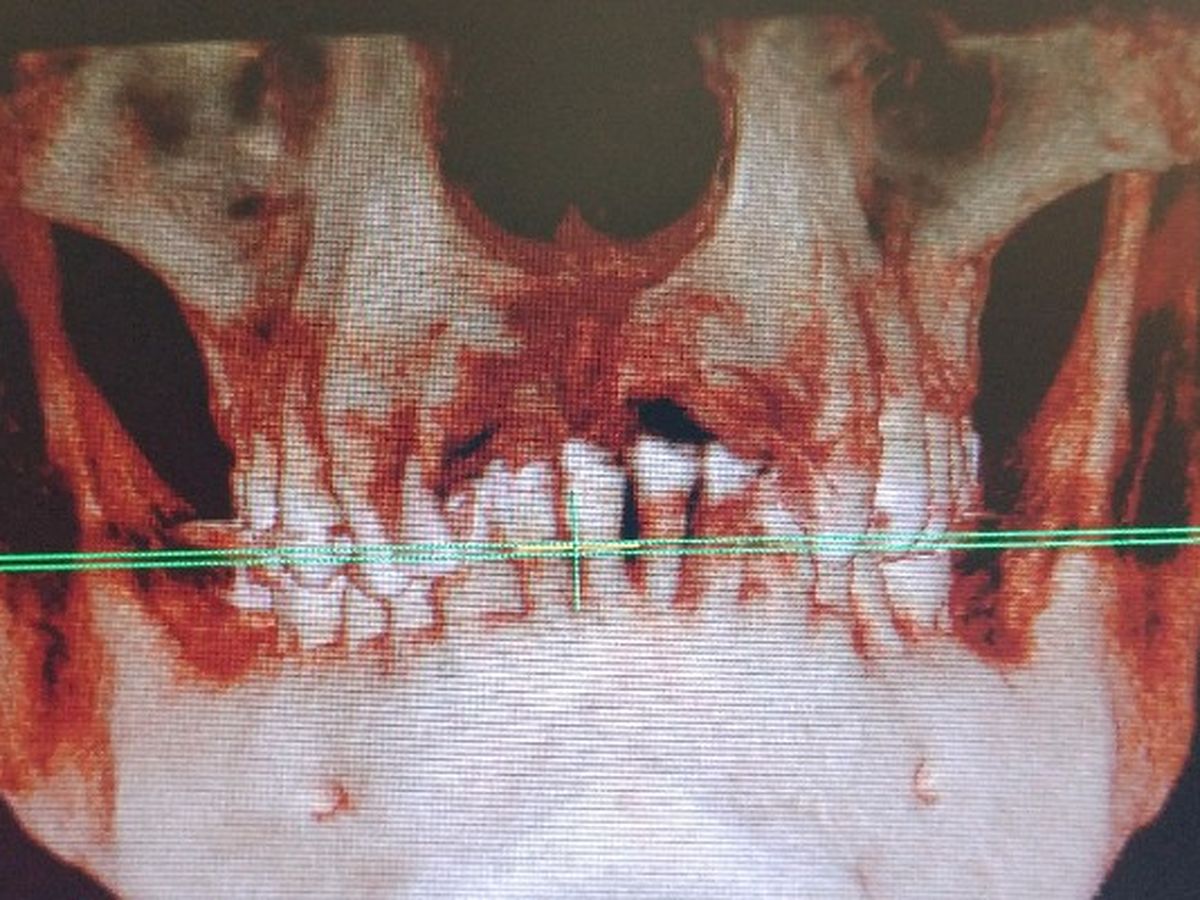

Daryls never been happy with his smile. This picture shows his lower jaw entirely inside his upper jaw...

His bottom teeth touch the roof of his mouth constantly cutting it open and causing issues throughout the day and even while he sleeps. Because of the overbite he cannot even properly bite food because none of his teeth line up.